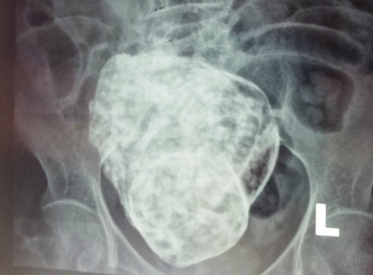

Để tìm ra chân tướng sự việc, bệnh viện đã mời một bác sĩ sản phụ khoa có thâm niên đến phụ trách kiểm tra. Sau khi thảo luận kỹ lưỡng, các bác sĩ đã đưa ra kết luận đáng ngạc nhiên: bào thai trong bụng bà Hoàng hóa ra là “bào thai đá” (Lithopedion). Đây là một hiện tượng hiếm gặp, xảy ra khi thai nằm trong ổ bụng bị chết và lưu lại trong cơ thể người mẹ lâu ngày rồi bị vôi hóa dần. Tỷ lệ thai trong ổ bụng khoảng 1/11.000 trường hợp thai kỳ, trong đó khoảng 1,5-1,8 % thai hóa đá.

Cụ thể hơn, các bác sĩ lý giải rằng: Bình thường trứng sau khi thụ tinh di chuyển và làm tổ trong buồng tử cung. Thai nhi sẽ tiếp tục phát triển để lớn lên. Tuy nhiên vì một lí do nào đó thai nhi bị chết và lưu lại trong cơ thể mẹ. Thường thì những thai nhi đó sẽ tự tiêu đối với những thai nhỏ, nhưng trong vài trường hợp một phần nào đó của thai nhi không thể tự tiêu hết mà phải nhờ đến sự hỗ trợ của bác sĩ. Tuy nhiên có vài trường hợp hiếm gặp thai nhi bị chết lưu không được loại bỏ hoàn toàn ra khỏi người mẹ. Theo thời gian thai nhi đó bị vôi hóa dần và trở thành thai đá.

Các bác sĩ suy đoán, có thể bà Hoàng đã từng mang thai một lần khi còn trẻ nhưng do nhiều nguyên nhân khác nhau, thai nhi không phát triển bình thường nên chết lưu. Trong tình huống bà hoàn toàn không nhận ra để loại bỏ khỏi cơ thể, bào thai đã trở thành “thai đá”. Cú ngã này có thể đã vô tình đụng vào “thai đá”, khiến bà bị đau bụng.